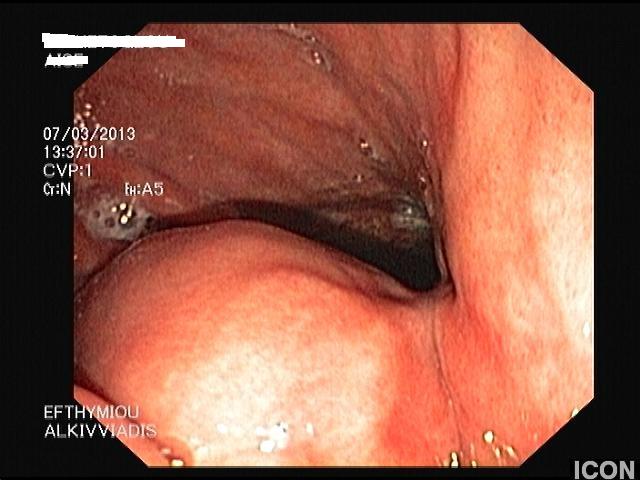

Γυναίκα 54 ετών εμφάνισε τους προηγούμενους 6-8 μήνες έντονη μυική αδυναμία και αδυναμία βάδισης και μετά τον ανάλογο κλινικό και εργαστηριακό έλεγχο τέθηκε η διάγνωση της μυασθένειας gravis. Στα πλαίσια της διερεύνησης, υποβλήθηκε σε αξονική τομογραφία (CT) θώρακος, άνω-κάτω κοιλίας και γαστροσκόπηση όπου διαπιστώθηκε ένας υποβλεννογόνιος όγκος διαμέτρου 5εκ στο σώμα του στομάχου. Η ασθενής παραπέμφθηκε για ενδοσκοπικό υπέρηχο και βιοψία (EUS-FNA). Στον ενδοσκοπικό υπέρηχο, o όγκος παρουσίαζε έντονη ανομοιογένεια του παρεγχύματος του, με υπερηχοϊκές περιοχές αλλά και υποηχοϊκές κύστεις. Τα όρια του ήταν σαφή, ομαλά, δεν εμφάνιζε εσωτερικές επασβεστώσεις και είχε έντονη αγγείωση. Ο όγκος προερχόταν από την 4η υπερηχογραφική στιβάδα του τοιχώματος, δηλ το μυικό χιτώνα. Έγινε βιοψία με λεπτή βελόνη 19g (FNA X 3) από διαφορετικές θέσεις της μάζας. Η ιστολογική εξέταση έδειξε ατρακτόμορφα κύτταρα με μέτρια ατυπία και η ανοσοϊστοχημεία έδειξε ήπια καθολική θετικότητα στο αντιγόνο c-kit και έντονη θετικότητα στο αντιγόνο CD34, ευρήματα συμβατά με στρωματικό όγκο πεπτικού. Η ασθενής παραπέμφθηκε σε χειρουργό για χειρουργική αντιμετώπιση.

Γαστροσκόπηση: υποβλεννογόνιος όγκος στομάχου